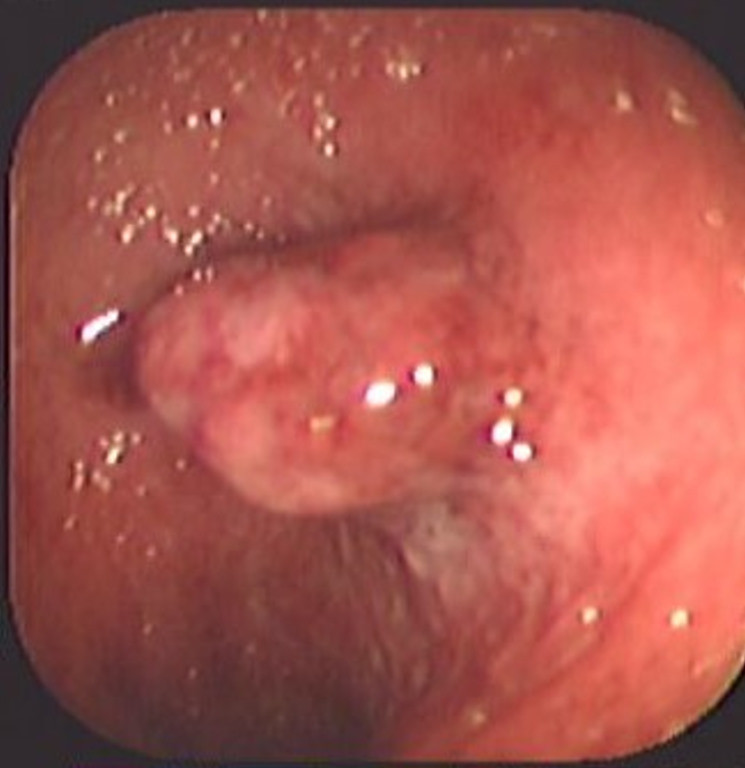

Colitis ulcerosa crónica inespecífica

Envíado por Dr. Carlos Ernesto Arévalo